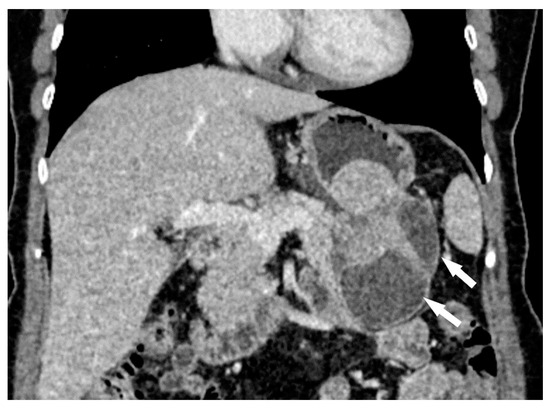

- Growth mode: exophytic/mixed and endophytic (Figure 1);